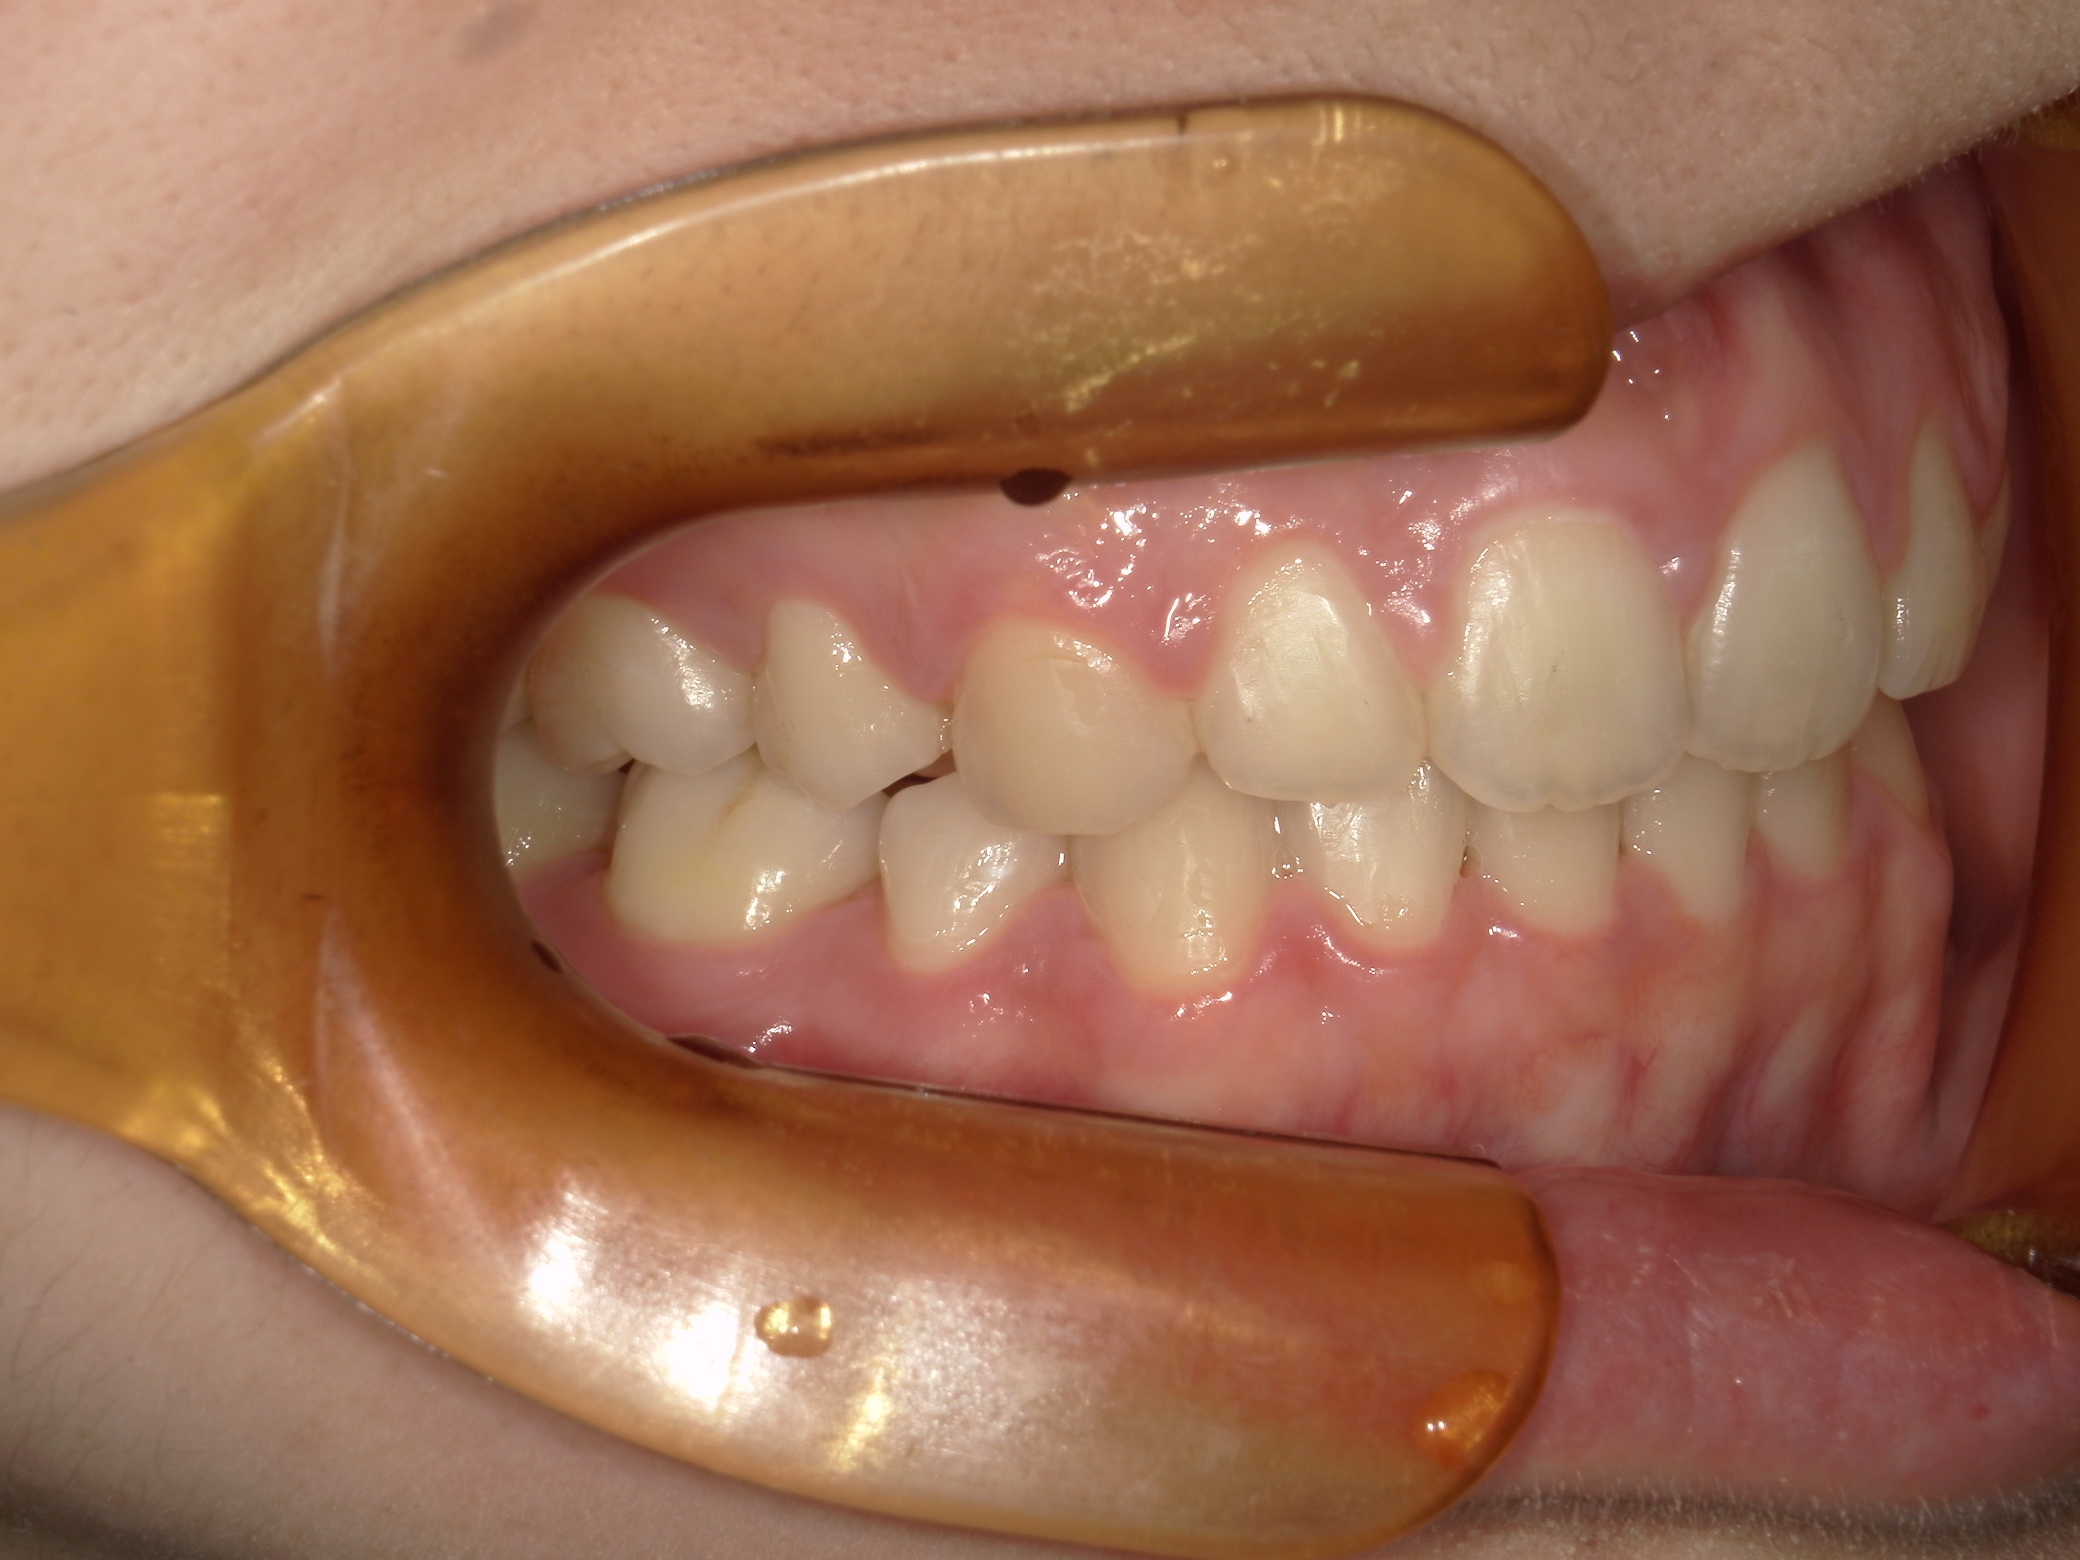

口内右

治療前

治療後